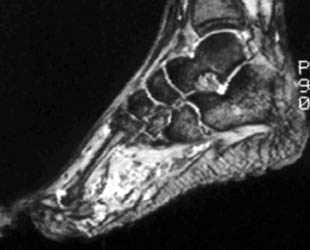

Typically divided into capillary (containing small capillary-like vessels) and cavernous (containing large sinusoids filled with blood) categories. Although lesions are most common in the skin and subcutaneous tissues, they also involve the muscles of the peripheral extremities. They are often irregular and have mixed signal intensity. Usually they are slightly higher in intensity than skeletal muscle on T1 and have markedly high intensity on T2 weighted sequences, with internal septa and slightly lobulated or irregular borders. Numerous serpiginous vessels may be seen.

39 year old male with an extensive soft tissue mass involving the plantar aspect of the foot, dissecting between the third and fourth metatarsals, and extending into dorsum of the foot. The mass has intermediate signal on T1 and very high signal on T2 weighted images, and appears serpiginous.